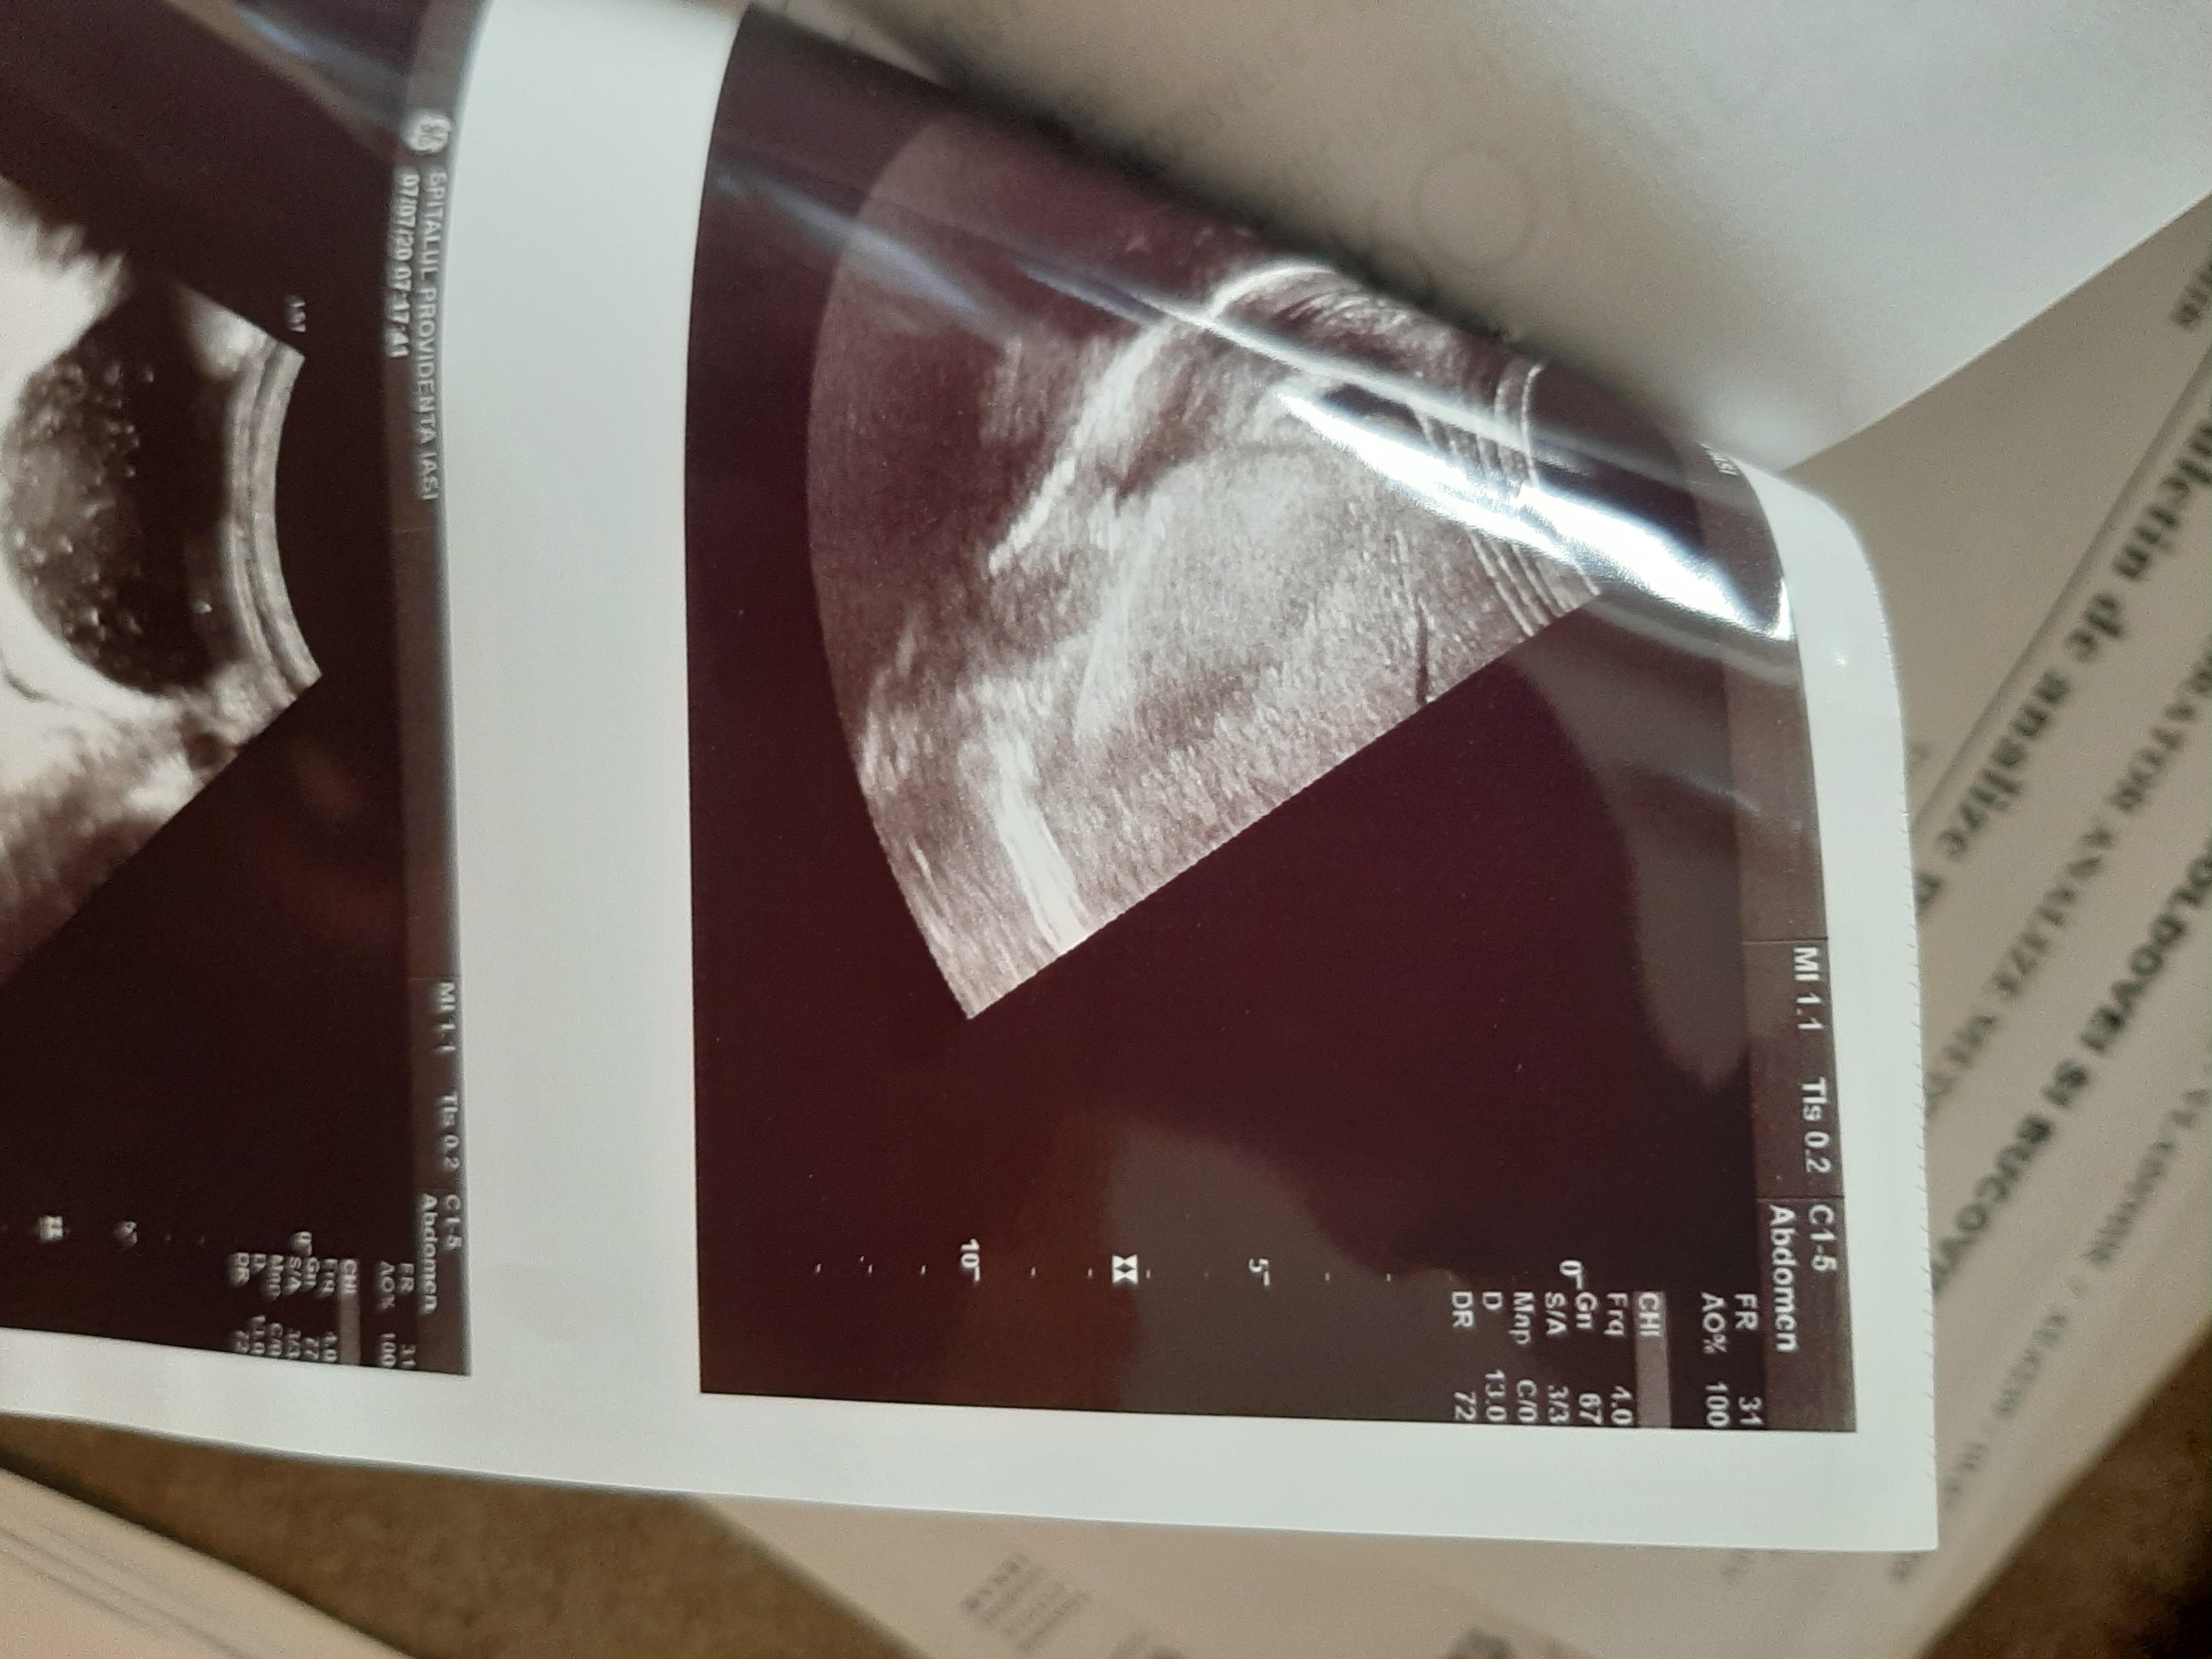

Diagnosticul medicilor a fost: sindrom hipoanabolic, litiază biliară veziculară, boală de reflux gastroesofagian, antecedente de colită repetată cu Clostridium Difficile.